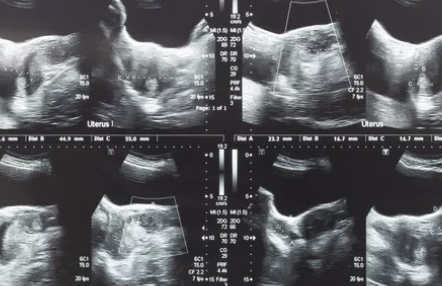

가장 기본은 산부인과 초음파 검사입니다.

필요 시 MRI나 자궁내시경을 통해

- 근종의 크기

- 위치

- 주변 장기 압박 여부

를 자세히 확인합니다.

정기 검진 시 발견되는 경우가 많아,

1년에 한 번 자궁·난소 초음파는 필수예요.